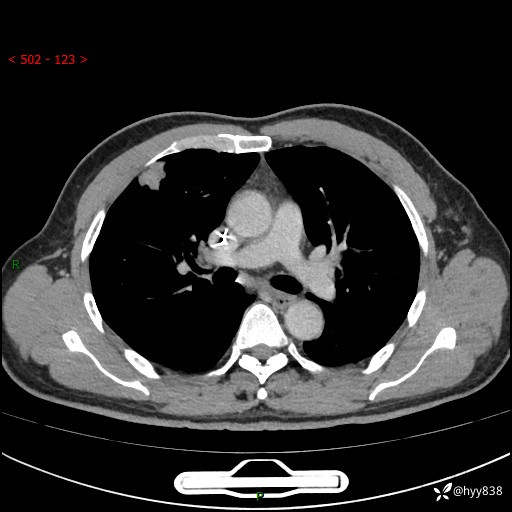

现病史:者10余天前因胸闷就诊于我院心血管内科,行胸部CT提示右肺上叶结节(24mm×16mm),考虑肿瘤性病变可能。无畏寒、发热、盗汗,无咳嗽咳痰,无咯血,无胸痛,无呼吸困难等不适,未予特殊处理。今为求进一步诊治,前来我院就诊,门诊以“肺结节待查”收住入院。 患者自起病来精神、食欲、睡眠尚可,体力下降,体重无明显变化。

胸部CT平扫+增强